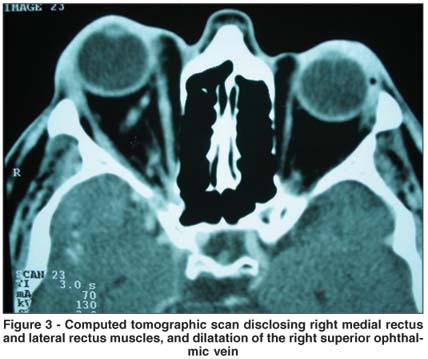

On examination, his visual acuity was hand motions in the right and 20/25 in the left eye. The right eye showed dilated episcleral vessels, lid swelling, conjunctival injection, chemosis, and 3-mm proptosis (Figure 1). Its motility was restricted in all directions. Intraocular pressure was normal, anterior chamber was deep, and the angle was open. A relative afferent pupillary defect was noted. Fundus examination showed evidence of CRAO with a diffuse pallor and cherry-red spot at the macula (Figure 2). Fluorescein angiography revealed a prolonged arm-to-retina circulation time of more than 1 minute, which was also compatible with the diagnosis of CRAO. The examination of the left eye was unremarkable. Hematological work-up was normal. A computed tomographic scan disclosed an enlarged right superior ophthalmic vein and thickening of extraocular muscles in the right eye (Figure 3). No abnormalities were demonstrated in the left orbit. Carotid angiography was performed once treatment was planned, and spontaneous closure of the fistula was noted (Figure 4). The patient's clinical findings improved gradually over the subsequent two months, however, no significant improvement in right eye vision was obtained. Excessive tarsal conjunctiva was excised with good cosmetic result.